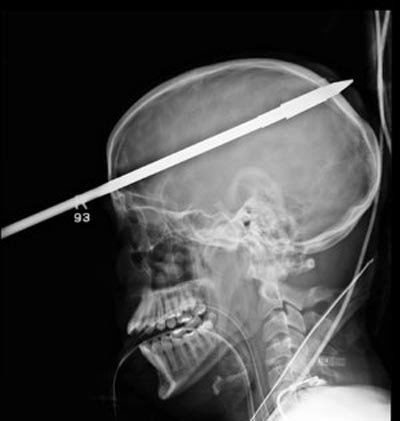

Các bác sĩ ở Miami, Mỹ đã gỡ bỏ thành công mũi tên vô tình đâm trúng hộp sọ của một thanh niên trong lúc đi dã ngoại.

Yasser Lopez, 16 tuổi, đang phục hội sau khi tình cờ bị trúng tên của một người bạn trong lúc đi câu cá ở Florida hôm 8/6.

Các bác sĩ tại Bệnh viện tưởng niệm Jackson tại Miami cho biết mũi tên dài 90cm đã đâm vào trán của Lopez, trên mắt phải 5cm và xuyên qua phía sau đầu.

Hiện Lopez có thể đi lại và nói chuyện sau khi trải qua ca phẫu thuật kéo dài 3 tiếng.

Sau khi cho Lopez dùng thuốc an thần, các bác sĩ phải cắt bỏ một phần của mũi tên i-nốc bằng máy cắt y tế để có thể tiến hành chụp CT (chụp cắt lớp vi tính có sự trợ giúp của máy tính) cho cậu.

"Thật là kỳ diệu mũi tên không đâm trúng tất cả các mạch máu chính của não," nhà giải phẫu thần kinh Ross Bullock nói.